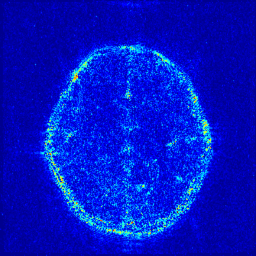

We take the difference between the absolute reconstruction error of zero-filled and the compared CS-MRI methods and only keep the nonnegative values, which can be formulated as

md=(|xfsx¯p||xfs𝒵(y)|)+.subscript𝑚𝑑subscriptsubscript𝑥𝑓𝑠subscript¯𝑥𝑝subscript𝑥𝑓𝑠𝒵𝑦m_{d}={\left({\left|{{x_{fs}}-{\overline{x}_{p}}}\right|-\left|{{x_{fs}}-{\cal Z}(y)}\right|}\right)_{+}}. (8)

Where the operator ()+subscript{\left(\cdot\right)_{+}} set the negative values to zero. We only keep the nonnegative values in the map, which results the filtered difference map. We show the corresponding filtered difference map mdsubscript𝑚𝑑m_{d} in figure 3 in the range [0 0.2]. The bright region means the better accuracy of zero-filled reconstruction. We observe the zero-filling reconstruction provide better reconstruction accuracy on some regions, indicating the information loss in the reconstruction occurs.

Figure 3: The filtered difference map d𝑑d between the reconstruction errors of the zero-filled reconstruction and recent CS-MRI inversions.